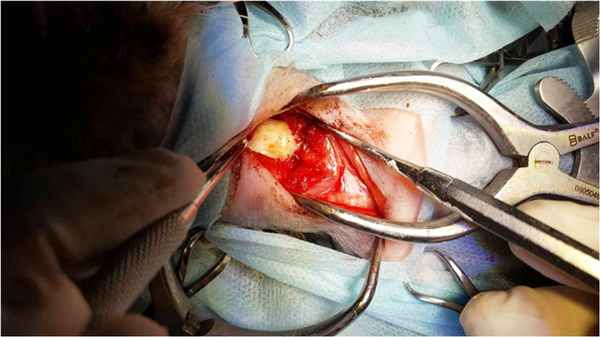

В клинике «Самарская Лука» используется хирургическая коррекция данной патологии с помощью вентральной стабилизации С1-С2 реперными или спицами Киршнера с последующей их фиксацией костным цементом.

Техника артродеза атланто-аксильного сустава включает трансартикулярную фиксацию, установку 3 имплантов с закреплением костным цементом. Суставные хрящи удаляются, производится тракция и репозиция компонентов сустава, после чего последовательно, устанавливаются 3 спицы через сустав С1-С2 и в тело С2. Закладку аутотрансплантанта, равно как и шейные послеоперационные корсеты мы не используем.

Интраоперационное - вентральная фиксация спицами Киршнера первого и второго шейного позвонка.

Укрытие металла костным цементом